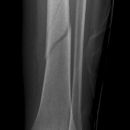

distaler Unterschenkelschaft

Spiralfraktur Tibia